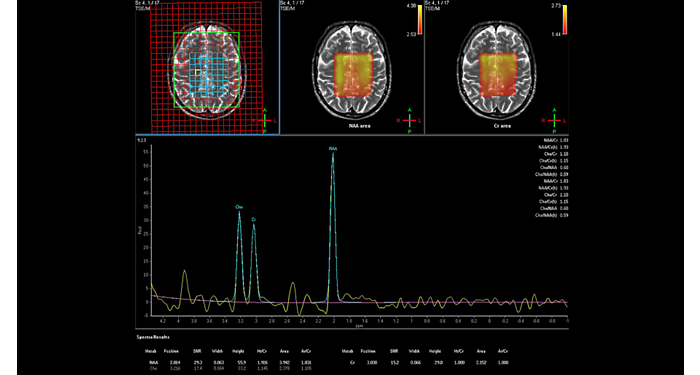

El 70% de los radiólogos consideran que las indicaciones neurológicas son un desafío, sobre todo debido a la falta de técnicas apropiadas de imagenología y visualización¹. Philips tiene como objetivo proporcionar la mejor claridad de diagnóstico posible y orientación terapéutica para todos los pacientes con trastornos neurológicos. Al aprovechar nuestra plataforma digital dStream, este año presentamos un conjunto de estrategias nuevas de imagenología y visualización. Esto puede ayudarlo a resolver preguntas sobre neurología complejas con mayor certeza, así como a desbloquear nuevos territorios neurológicos en aplicaciones neurofuncionales avanzadas. Este es un paso clave para aumentar el diagnóstico neurológico y, en última instancia, impactar más vidas con la RM. ¹ TMTG Market Survey 2016

Nuevas aplicaciones neurológicas